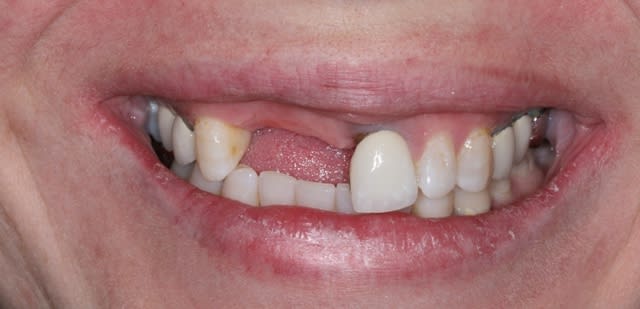

Patiente de 30 ans suite à parodontite a perdu 11-12 avec grosse perte osseuse.

J'ai suffisamment d'os pour prévoir la pose implantaire sans greffe mais esthétiquement je pense que cela va être moche car la ligne du sourire me semble bien haute.

si tu implantes comme ça, on est bien d'accord que ça va être moche.

que comptes tu faire de la 21? as tu une rétro?